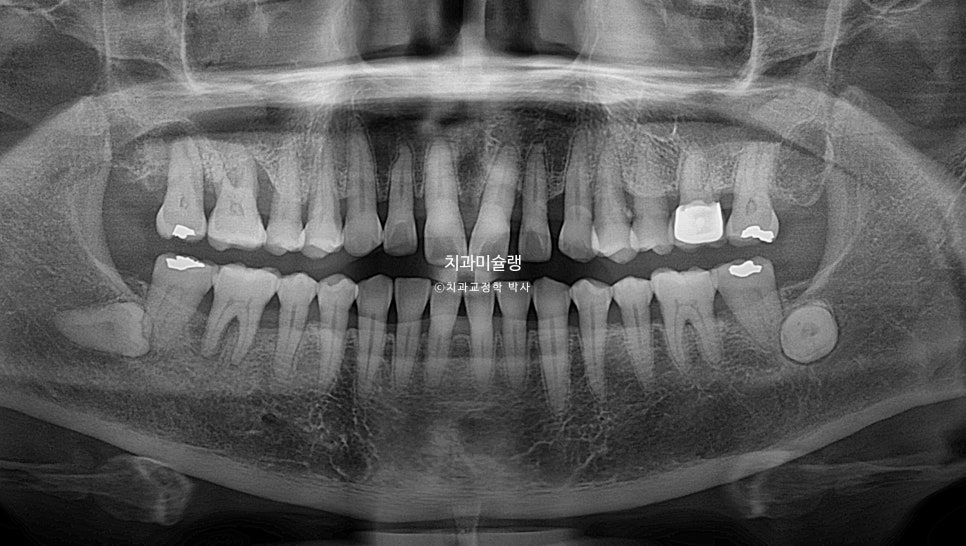

노년교정에서의 중요한 고려사항은 무엇보다 잇몸건강 이죠. 엑스레이상 잇몸이 내려앉은 부분이 여기저기 보이고 뿌리끝 염증이 있는 어금니도 보입니다.

이러한 치주염 환자에서는 교정치료 전 잇몸치료가 선행이 되어야 합니다.

치근흡수는 없으며, 기울어져있던 앞니 치축이 개선되었습니다.